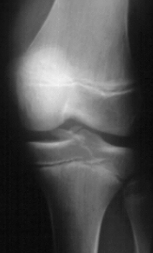

- XRAYS: Type III Meyer's / McKeever tibial spine fracture

CLASSIFICATION:

- Meyer's and McKeever have described three main types of intercondylar

fractures in children based on the amount of displacement and the fracture

pattern seen on the initial radiographs. Type I is nondisplaced and does

not interfere with knee extension. The type II fracture has a posterior

hinge with the anterior portion being elevated. In this type, knee extension

is generally limited, and there is a possibility that the anterior horn

of the meniscus is caught under the anterior fracture fragment. A type

III fracture is fully displaced, usually with the knee held in a mildly

flexed position.

RADIOGRAPHIC FINDINGS:

- Adequate AP and Lateral x-rays are essential to evaluate the degree

of displacement of the anterior tibial spine.

- Fracture is best seen on the lateral radiograph.